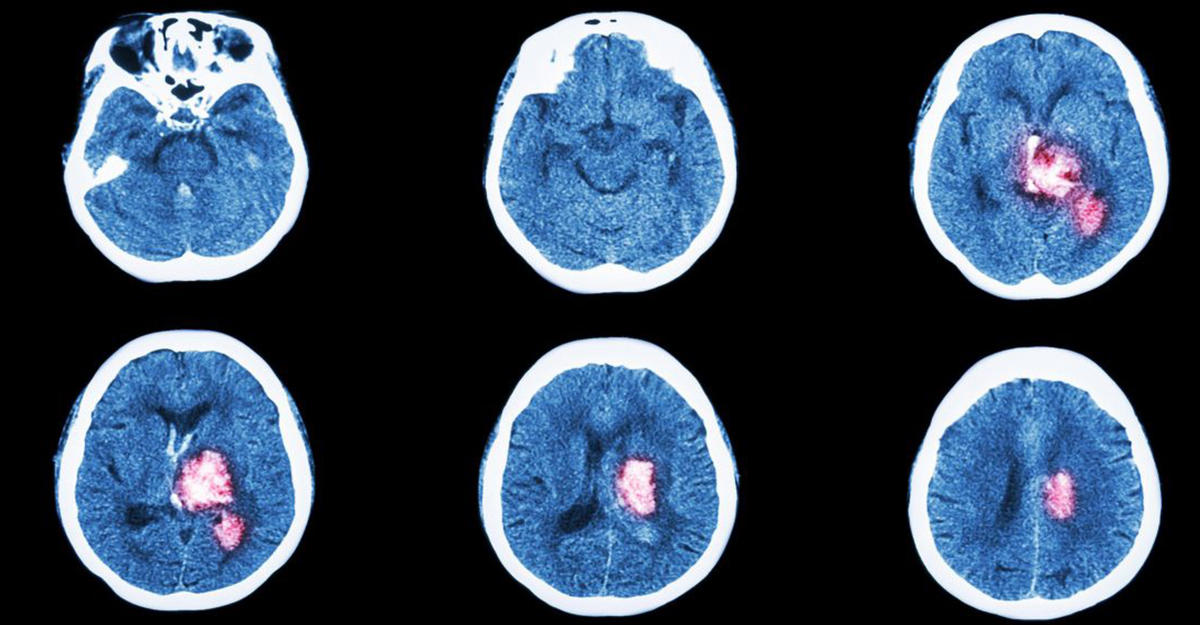

Инсульт - это нарушение кровообращения мозга. Когда кровь не поступает к клеткам (из-за тромба или разрыва сосуда), они погибают. Из-за этого человек утрачивает способности: двигаться, говорить, видеть, дышать.